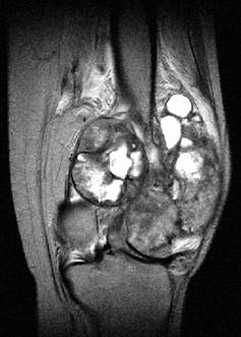

Магнитно-резонансная томография

МРТ позволяет тщательно стадировать и оценить распространенность опухоли перед резекцией конечности, особенно при оценке внутрикостного распространения опухоли и вовлечения в процесс окружающих мягких тканей, важна при оценке пластинки роста, поскольку до 75-88% метафизарных опухолей пересекают эпифизарную пластинку роста [4].

- T1

- мягкие ткани неминирализованного компонента: промежуточная интенсивность МР сигнала

- минерализованный / обызвествленный компонент: низкая интенсивность МР сигнала

- перифокальный отек: промежуточная интенсивность МР сигнала

- разбросанные области кровоизлияний будут иметь различную интенсивность МР сигнала в зависимости от стадии распада продуктов гемоглобина

- контрастное усиление: повышение МР сигнала от солидного компонента опухоли

- мягкие ткани неминирализованного компонента: высокая интенсивность МР сигнала

- перифокальный отек: высокая интенсивность МР сигнала